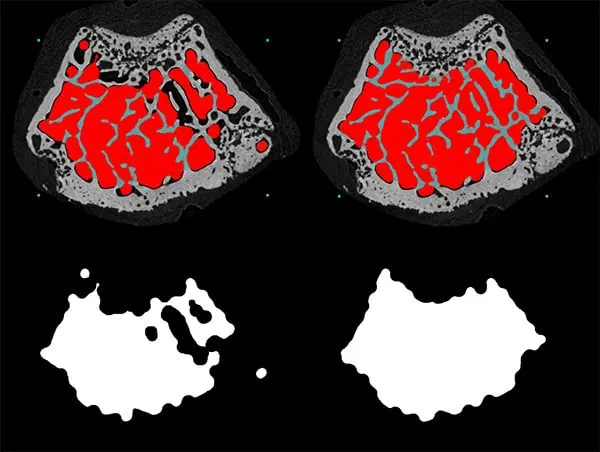

The image below shows the results after opening and closing to a radius of 12 voxels. The example on the left used a single open-close morphological operation and on the right the stepwise morphological escalator.

In the example above, the morphological escalator has successfully excluded peripheral remnants of growth plate from the trabecular VOI, including finely textured, porous regions of the cortical boundary. This restricts the analysis to mature secondary trabecular bone. This would not always be possible using standard trabecular-cortical separation algorithms.